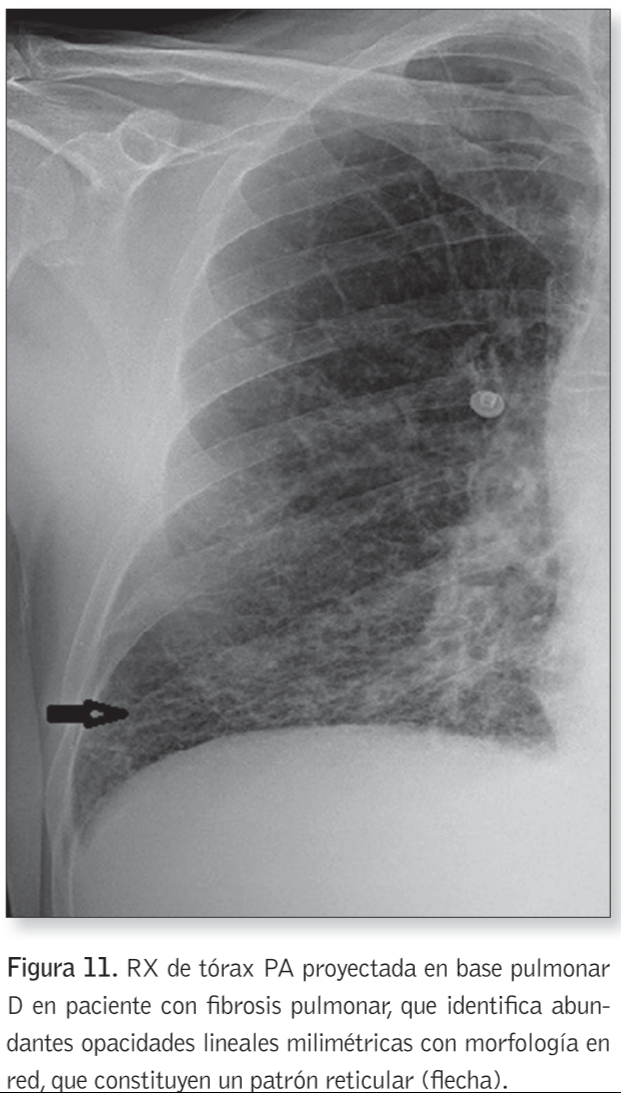

2) Patrón reticular

¿Cuándo se presenta el patrón reticular?

Enfermedades infiltrativas difusas